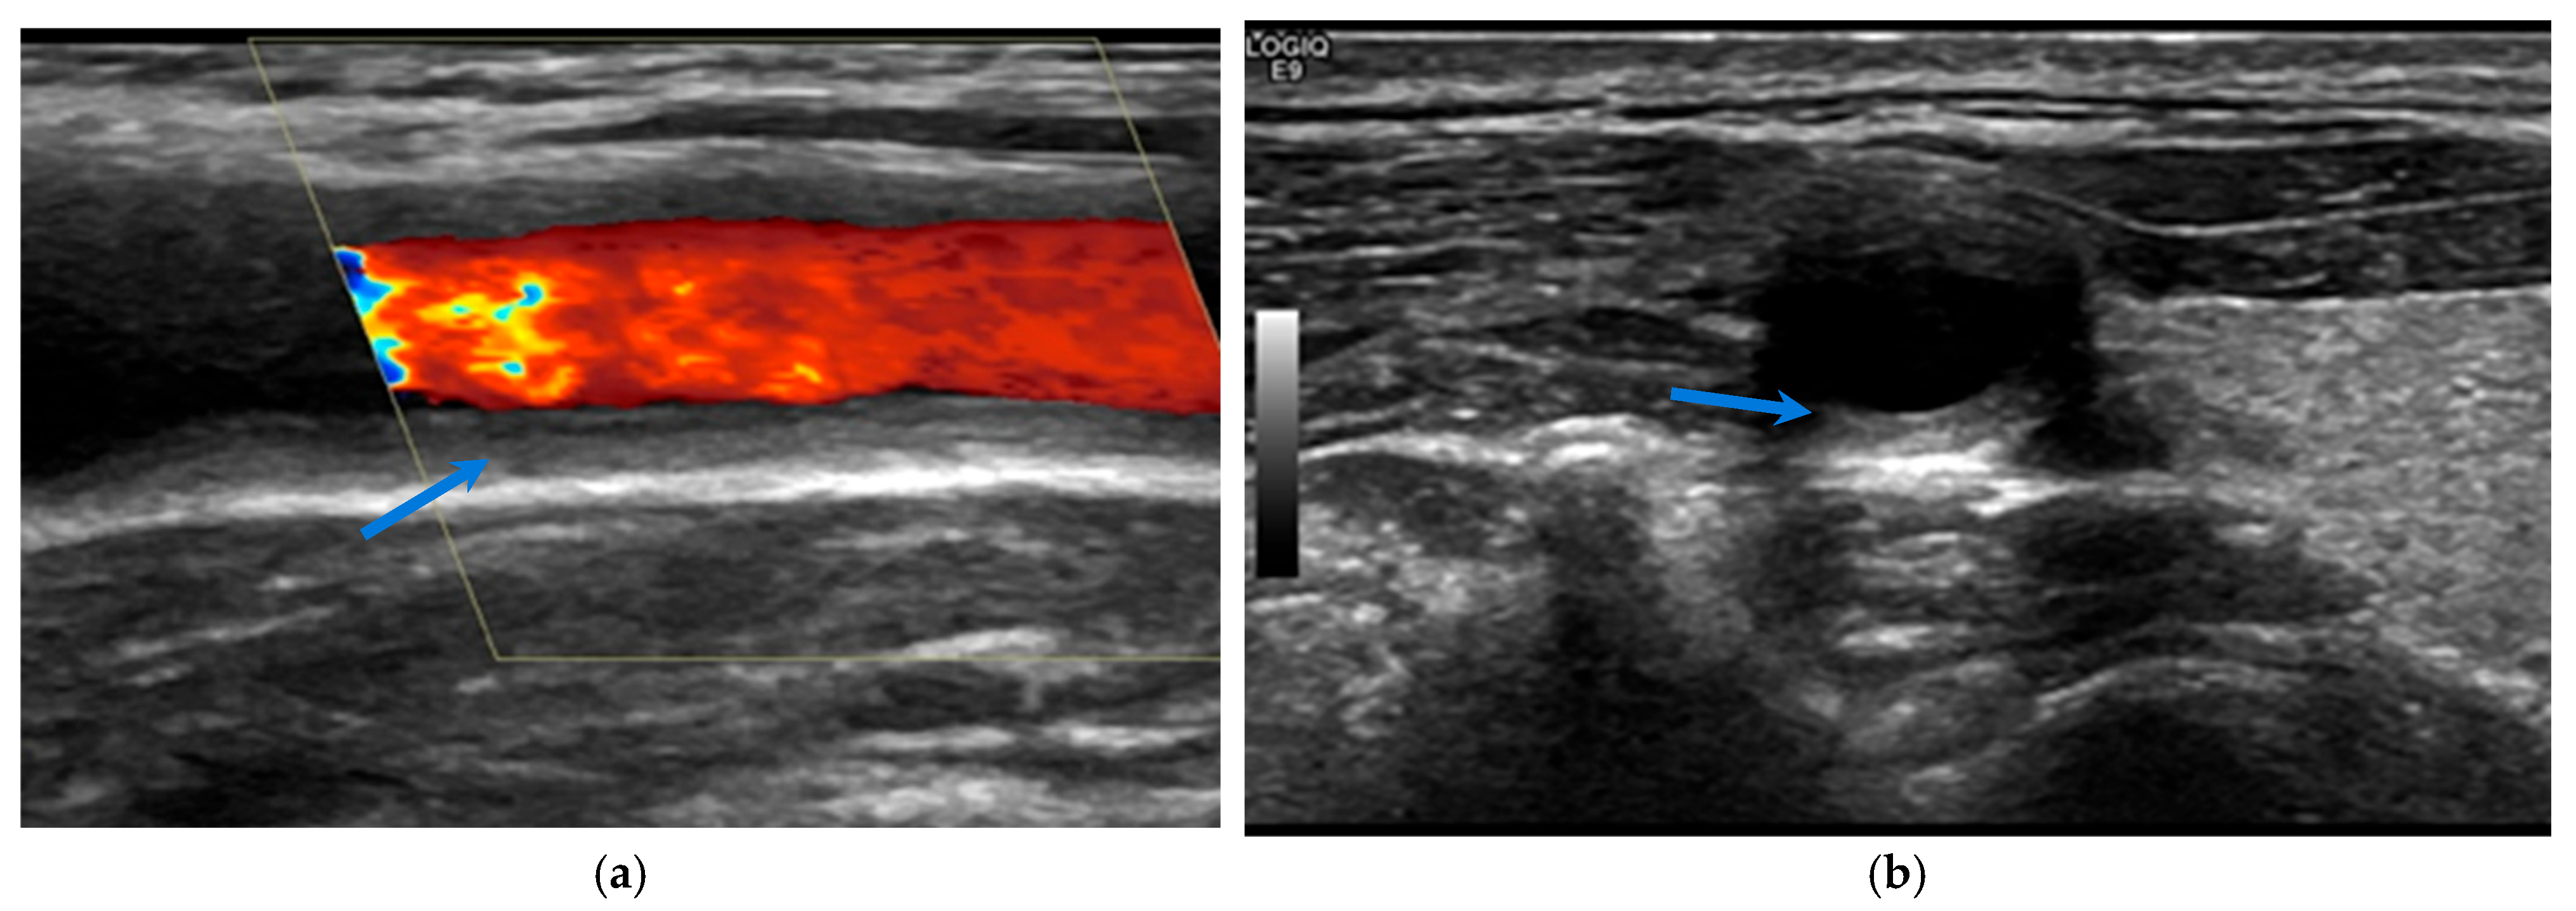

| Ultrasound | High for superficial arteries; limited for deep vessels. | Moderate–high, mostly based on halo and macaroni signs. | Sensitive to inflammatory changes (wall thickness and halo sign). Responsive under IL-6 blockade. Enables evaluation of structural damage. | Non-invasive, radiation-free, cost-effective, repeatable. | Operator-dependent; limited resolution for deep vessel evaluation; uncertain significance of residual or subclinical vascular changes. |